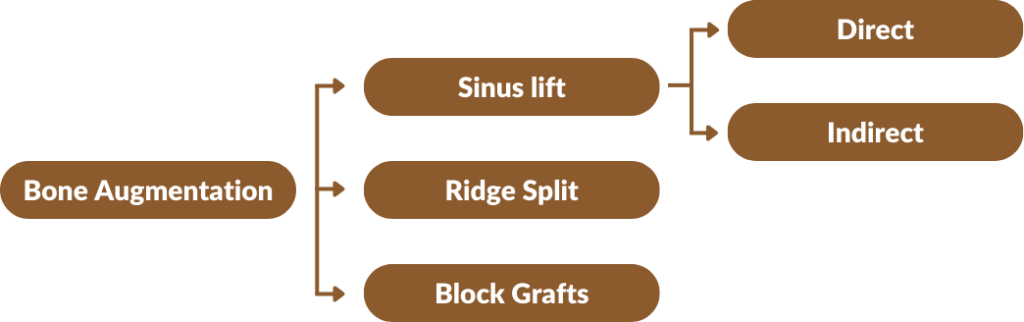

- Insufficient bone for placement of implants.

- The sinus pneumatized, causing insufficient bone height.

- Insufficient facial bone in the esthetic zone.